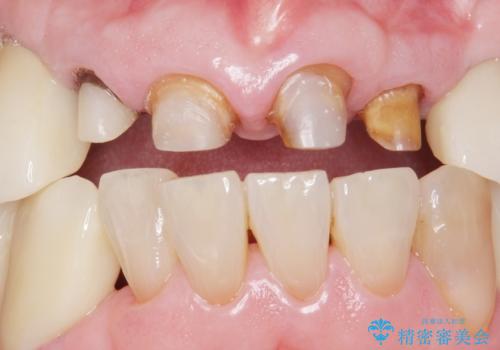

前歯4本のうち3本の被せ物が脱離し、残りの1本の被せ物は劣化し変色していました。

古い被せ物や土台・虫歯をしっかり除去したのち、セラミック治療を行いました。

患者様のご希望により、根尖病変の明らかな左上2のみ根管治療を行いました。